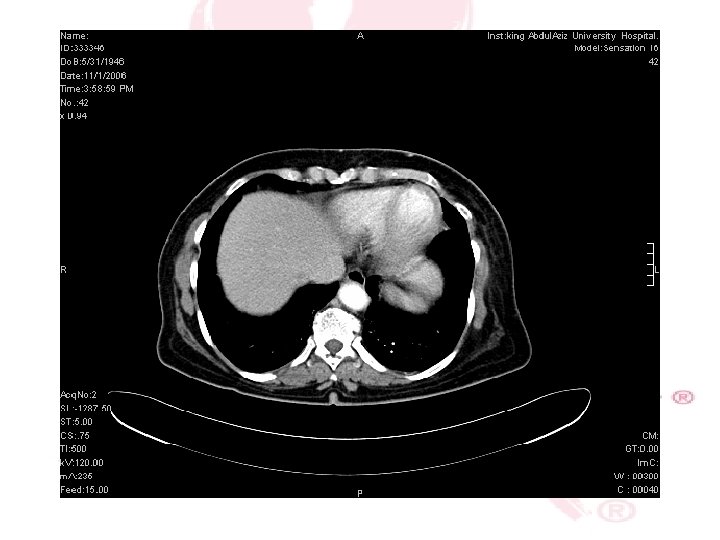

CT SCAN CHEST , ABDOMEN &PELVIS